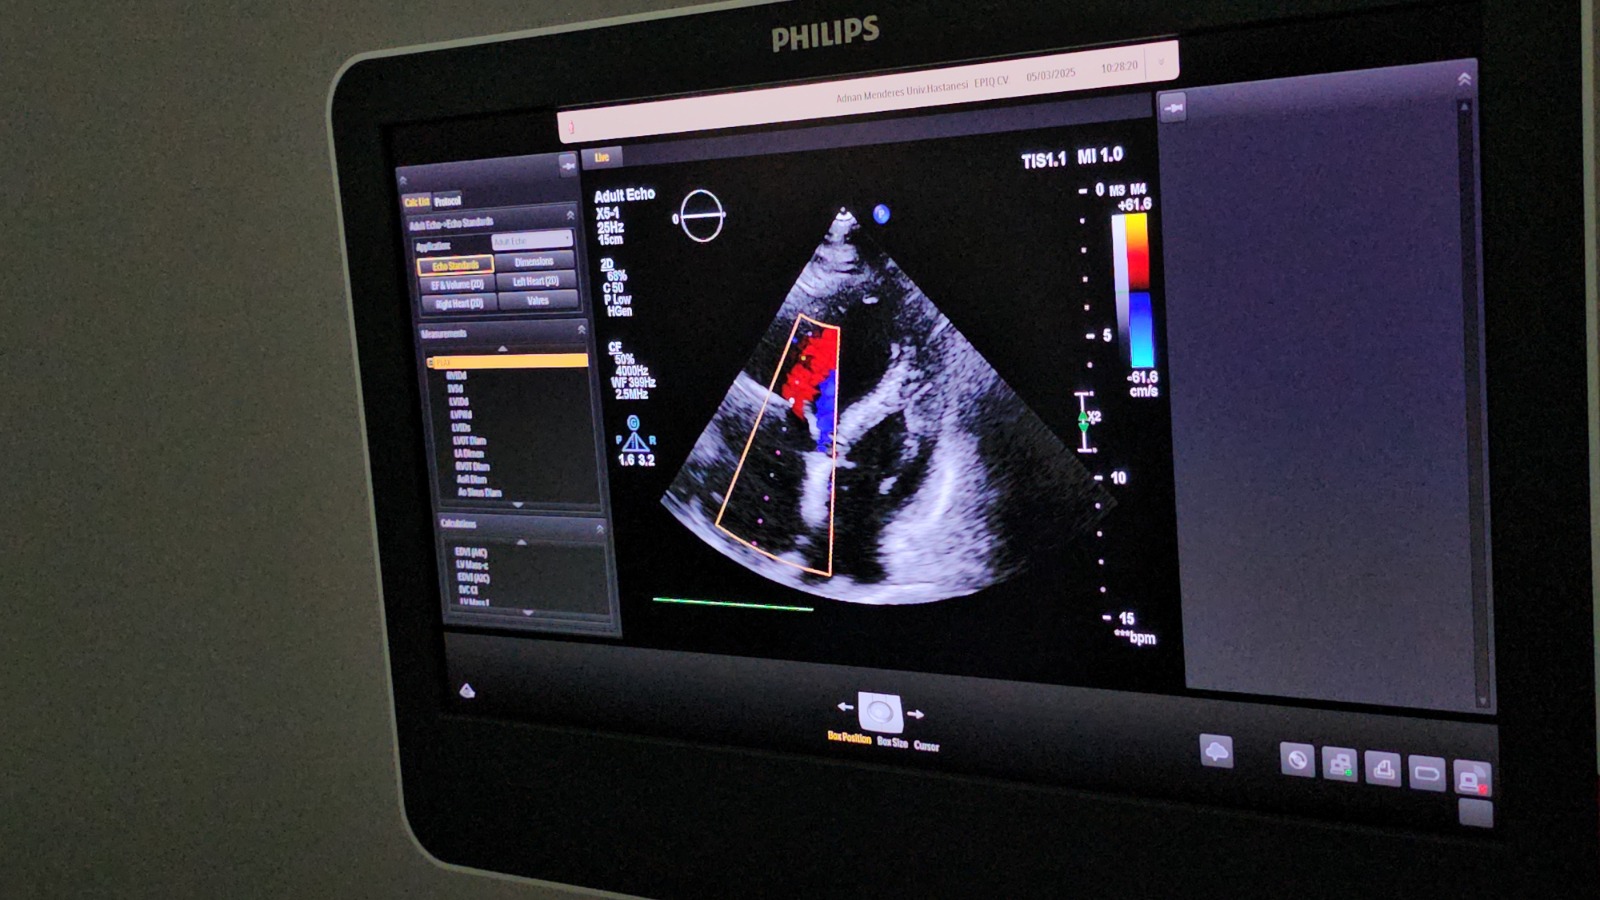

ADÜ Hastanesi Başhekimi Prof. Dr. Mücahit Avcil'in önderliğinde, Kardiyoloji Ana Bilim Dalı öğretim üyeleri Doç. Dr. Cemil Zencir ve Dr. Öğr. Üyesi Sevil Gülaştı tarafından gerçekleştirilen bu önemli operasyon, daha önce kifoplasti-vertebroplasti işlemi geçiren hastanın damarlarına sızan dolgu maddesi (sement) nedeniyle ortaya çıktı. Dr. Öğr. Üyesi Sevil Gülaştı, hastanın tekrarlayan nefes darlığı şikayetleriyle acil servise başvurduğunu ve yapılan tetkikler sonucunda sementin kalbe kadar ulaştığının tespit edildiğini belirtti. Bu durumun hayati risk taşıması nedeniyle hasta, multidisipliner bir yaklaşımla değerlendirildi.

Doç. Dr. Cemil Zencir, ilk etapta cerrahi müdahale düşünülse de, hastanın yüksek risk taşıması sebebiyle özel olarak modifiye edilmiş bir kateterle sağ boyun toplardamarından girilerek yabancı cismin kapalı yöntemle çıkarılmasına karar verildiğini ifade etti. Zencir, "Hastamızın durumu birçok branşla değerlendirildi. Bu tür girişimlerde hastanın güvenliği önceliklidir. Sementin mukavemet gücünü değerlendirdikten sonra uygun yöntemi belirledik ve kapalı bir teknikle tek parça halinde çıkardık. Bu önemli girişim, bilindiği kadarıyla Türkiye'de ilk kez Üniversitemiz Hastanesinde başarıyla gerçekleştirildi." dedi.